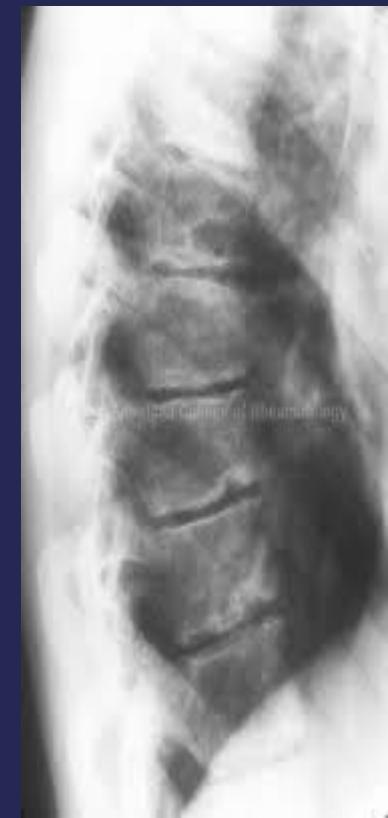

Senile Osteoporosis

- Pathology: Anterior wedge compression of several vertebrae

- Result: Rounded back in elderly people

- Irregular ossification of vertebral body epiphysis

- Central herniation of disc material into the body (Schmorl’s Node)

- Wedging of vertebrae

Pathology